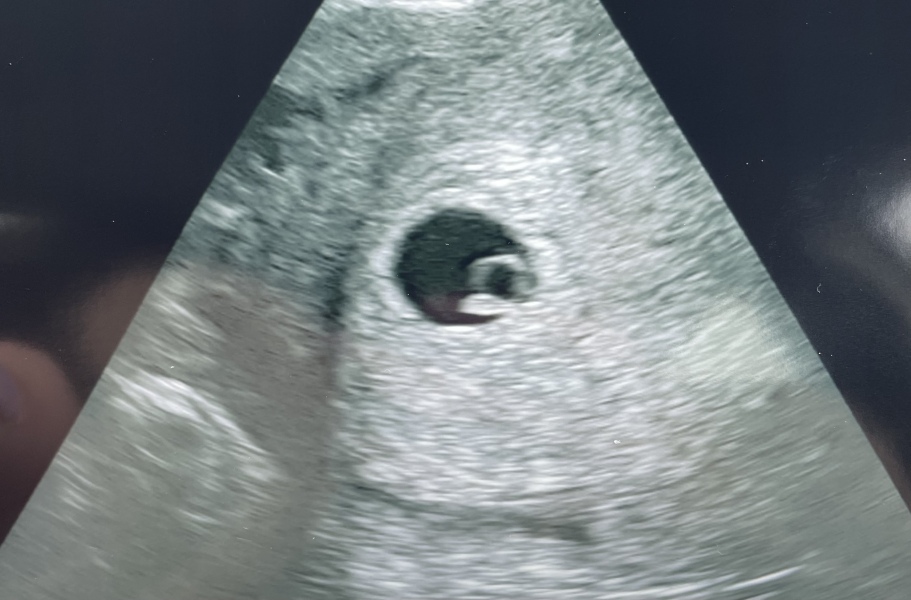

Hi just updating we had our scan tonight, baby measuring perfect at 6 weeks, saw the heartbeat, feels more real now x

@Mummy1502 oh my! Little baby bean🥰❤️ so so happy for you no more stressing just enjoy it now x

@Mummy1502 aww look 🥰 so cute exactly what we wanna see👌❤️x